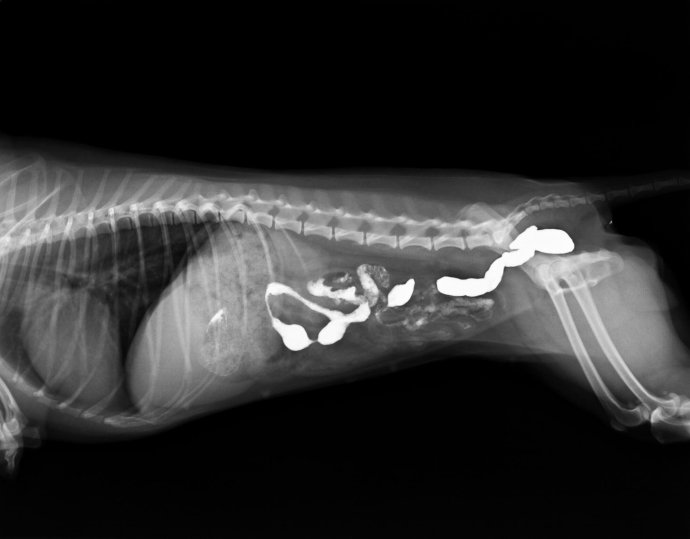

第三天,又出现呕吐,精神较差,做CR检查,发现腹部胃内有一核状异物。但体外触诊不明显,但是胃部敏感。于是手术探查。

CR结果如下: